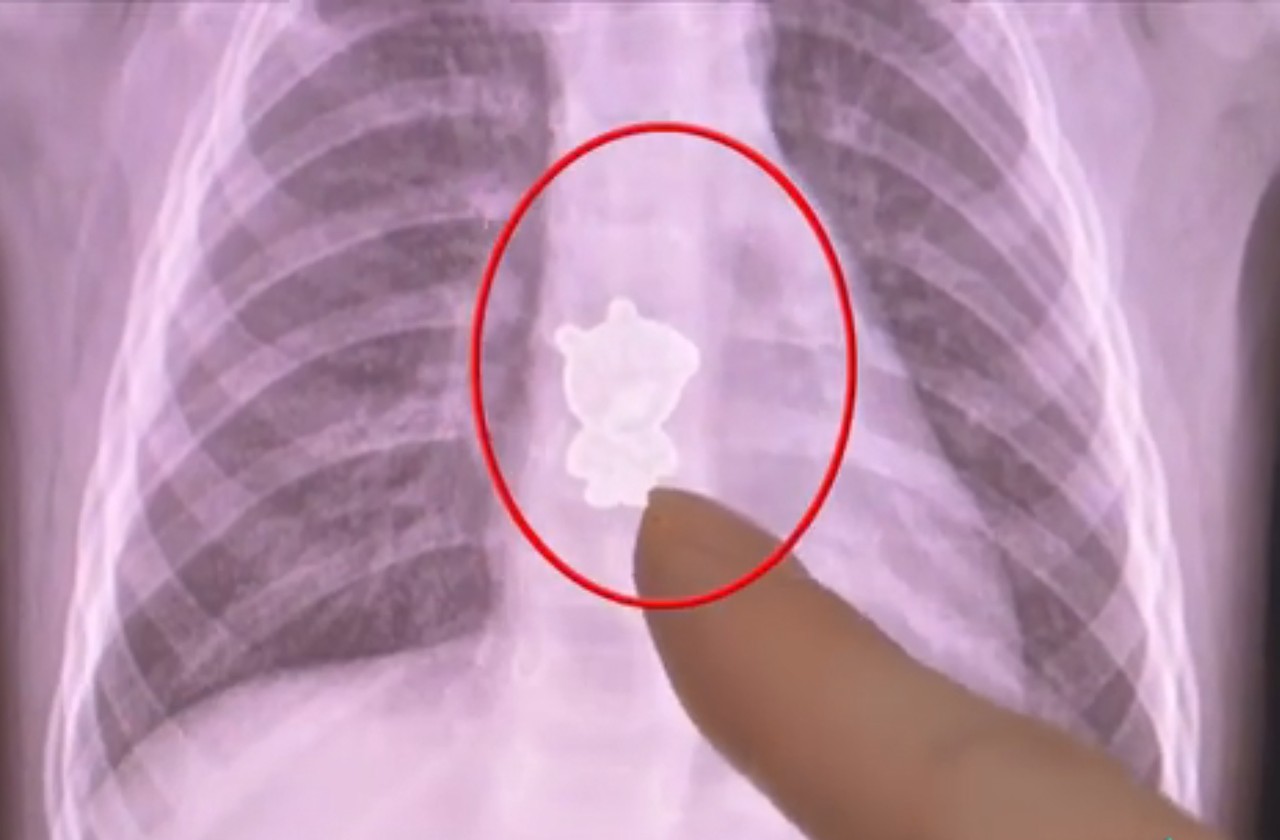

▲1歲女童食道內拍出「佩佩豬」。(圖/翻攝自政法頻道,下同)

湖南長沙一名1歲女童24日早上起床後開始不斷哭鬧,家長到處都檢查了,但是找不出原因,帶到醫院拍攝CT(電腦斷層掃描)之後,竟然在影像中出現了一個「佩佩豬」(粉紅豬小妹,Peppa Pig),趕緊進行手術。

綜合陸媒報導,悅悅(化名)24日早上開始不斷哭鬧,咳嗽還帶血絲,家屬見狀趕緊送她到醫院,醫生經過檢查發現,她的食道中下段有一個金屬的「佩佩豬」陰影,這才導致她不舒服,所幸經過手術已經順利取出。